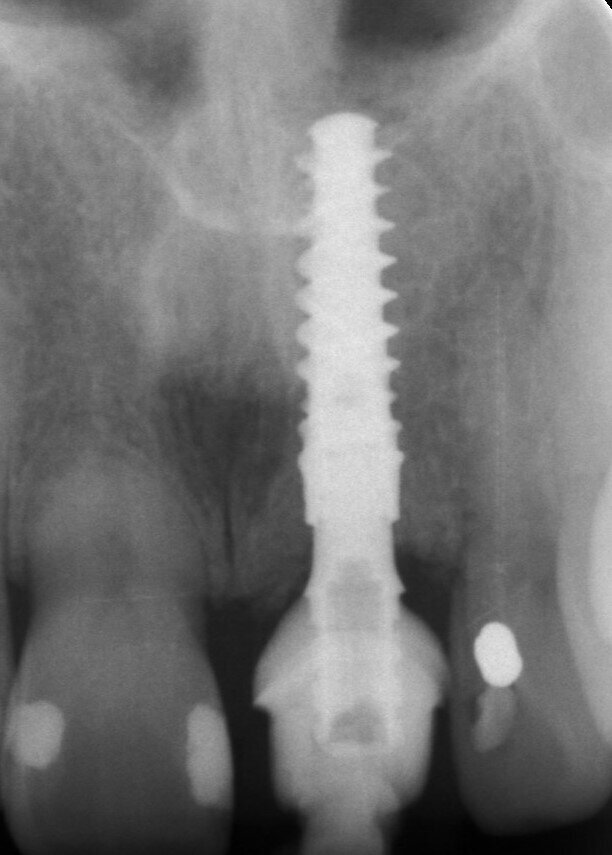

Una paziente di 53 anni si è presentata in studio con un incisivo sinistro fratturato a cui era stata più volte cementata una corona di ceramica (Figg. 1, 2). L’anamnesi e gli esami hanno evidenziato una buona salute sistemica e orale, un’occlusione ben equilibrata e nessuna abitudine al fumo. La tomografia cone beam (CBCT) e la radiografia periapicale hanno mostrato un riassorbimento radicolare esterno con inserimento nell’osso alveolare molto scarso, insufficiente per un adeguato posizionamento di un comune perno endocanalare (Figg. 3, 4). Considerando che il dente fratturato si trovava nella zona estetica, il paziente richiese un restauro nel modo più sicuro e più veloce possibile.

Fig. 3_Radiografia periapicale pre-operatoria.

La fresa preliminare da Ø 2,2 mm è stata utilizzata sulla rispettiva lunghezza prevista dall’impianto, seguita da un perno di allineamento per controllare l’orientamento in 3D (Figg. 6, 7). Le frese da Ø 2,8 mm e Ø 3,2 mm sono state utilizzate per completare l’osteotomia (Fig. 8). Il sito è stato quindi opportunamente sondato per valutare la possibile perforazione della parete. Un impianto 4×14 mm è stato posizionato, a partire dalla maniglia chirurgica che coinvolge la parte apicale dell’impianto, seguendo lo stesso orientamento dell’ago perforatore e correggendo la direzione dell’impianto mentre si spostava all’interno dell’osteotomia (Figg. 9, 10). La stabilità primaria (45 Ncm) è stata raggiunta nella posizione finale.

Un abutment provvisorio di Ø 4 mm con un’altezza gengivale di 2,5 mm è stato posizionato sull’impianto e non ha mostrato interferenze sulla cresta ossea, consentendo un adeguato profilo di emergenza (Fig. 19). Il guscio del dente, che è stato progettato e fresato in PMMA prima della procedura (Figg. 20, 21), è stato testato per assicurarsi che i contorni e le ali di ritenzione fossero adeguati e non causassero interferenze (Figg. 22, 23). Il lato palatale, comprendente una piccola porzione del bordo incisale, è stato aperto per consentire l’accesso al canale della vite (Figg. 24, 25). Le ali laterali del guscio del dente permettono alla corona provvisoria di rimanere immobile durante la procedura di prelievo, problema comune che i medici si trovano ad affrontare quando eseguono la tecnica pick-up immediata. Il guscio del dente è stato incollato al moncone provvisorio con composito flow fotopolimerizzabile ed è stato lasciato un sottile profilo di emergenza sulla porzione sottogengivale con lo stesso materiale (Fig. 26). A questo punto, le ali di ritenzione sono state rimosse. Senza compressione sui tessuti molli, la corona provvisoria è stata posizionata e il bordo incisale è stato ritoccato per garantire che il dente antagonista non lo toccasse nei movimenti di escursione. La corona provvisoria è stata cementata con un torque di 25 Ncm e il foro di accesso della vite è stato chiuso e lucidato correttamente (Fig. 27). Il paziente è stato visitato sette giorni dopo per il controllo radiografico postoperatorio e periapicale (Figg. 28, 29).

Fig. 29_Radiografia periapicale una settimana dopo l'intervento.

Fig. 33_Radiografia finale.